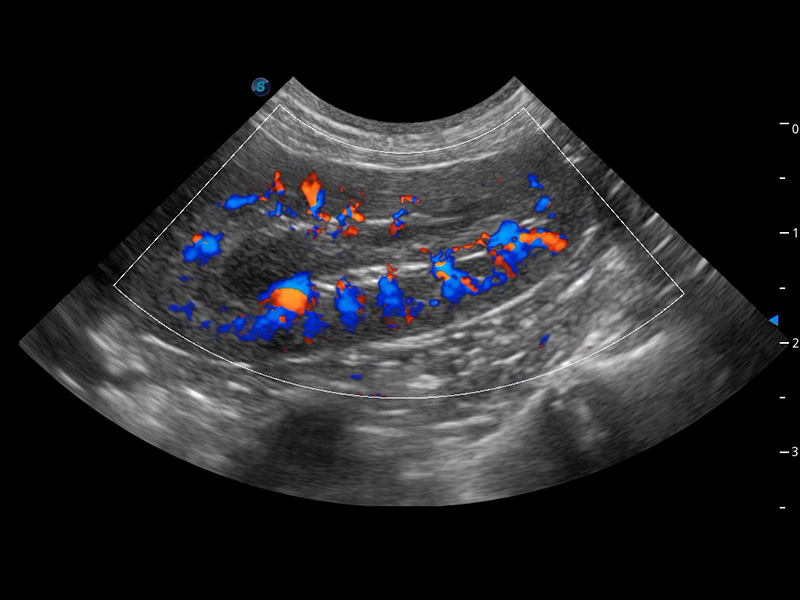

ProPet 60 作为一款高端台式动物超声设备,为动物医生的日常诊断提供了一系列贴合动物临床需求、解决临床实际问题的高级成像功能。凭借全系列高清探头,满足医生对腹部、心脏、生殖、浅表、肌骨等成像的所有需求,切实帮助您提升检查效率,提高诊断信心。

动物是人类最亲密的朋友和最值得信赖的伙伴。竞技宝(JJB)官方网站也一直致力于探索动物专用的超声影像解决方案。 全新推出的ProPet系列,是竞技宝(JJB)官方网站在动物超声影像智能化、专业化、精准化的一次跨越式革新。动物不能用言语来表述自己的不适,通过超声影像,ProPet系列搭建了动物医生与不同物种沟通的“桥梁”,为动物医生注入了“治愈之力”。